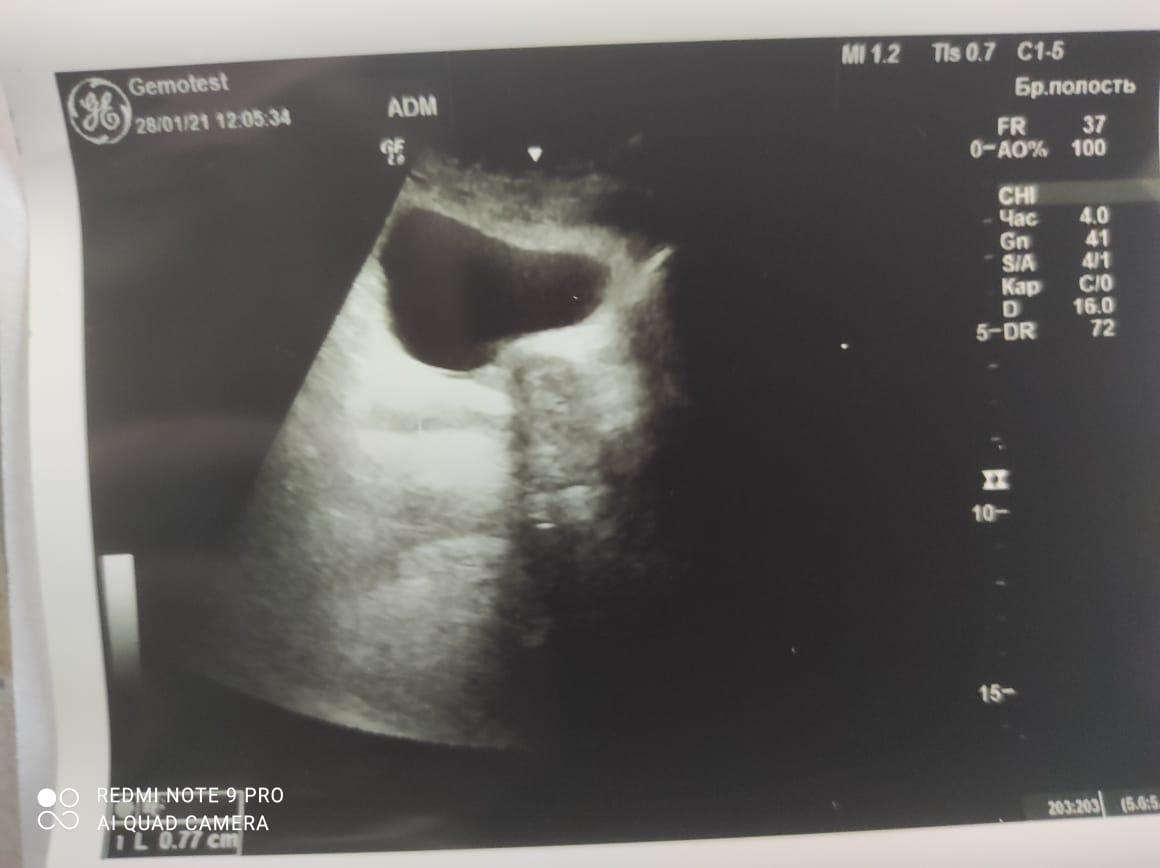

Здравствуйте! При наличии коралловидного камня правой почки(заключение УЗИ), можно предположить причиной боли нарушение уродинамики верхних мочевых путей), что, однако, не подтверждается результатами УЗИ почек( ЧЛС не расширена). Другая, наиболее вероятная возможная причина "боли в боку" - может быть патология опорнодвигательного аппарата. Необходимо проконсультироваться с неврологом и урологом очно, и согласовать возможность применения противовоспалительных, обезболивающих и спазмолитических препаратов - как первый шаг. В дальнейшем необходимо планировать возможное дальнейшее обследование и лечение. Удачи!